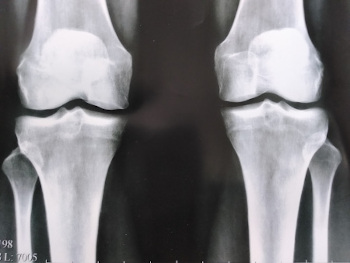

"ZAPAMTITE: ARTRITIS UNIŠTAVA HRSKAVIČKO TKIVO ZA 3 GODINE" Tako je rekao moj ljekar i stvarno sam završila u invalidskim kolicima! Užasna istina!

„Zašto ste ranije zanemarili simptome? Imate artrozu, artritis! Ako ne želiš da postaneš invalid, moraš hitno na operaciju kuka i koljena!"

Zamjena zgloba je veoma skupa i veoma ozbiljna operacija.

ZAPAMTITE: ARTRITIS I ARTROZA UNIŠTAVAJU HRSKAVO TKIVO ZA 3 GODINE! Nažalost, ne postoji lijek za artrozu, samo će vam operacija pomoći...